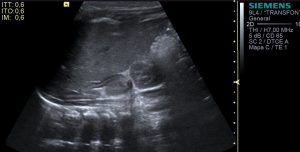

Mira:

En la imagen 1 su anatomía, que es primordial y además me tiene loco perdido. El Gemelo y el Semimembranoso, profundo al Semitendinoso, que si los continuas en eje corto hacia próximal van a ser dos supermúsculos de la parte posterior del muslo. Y el cuello, del quiste que es muy bonito también.